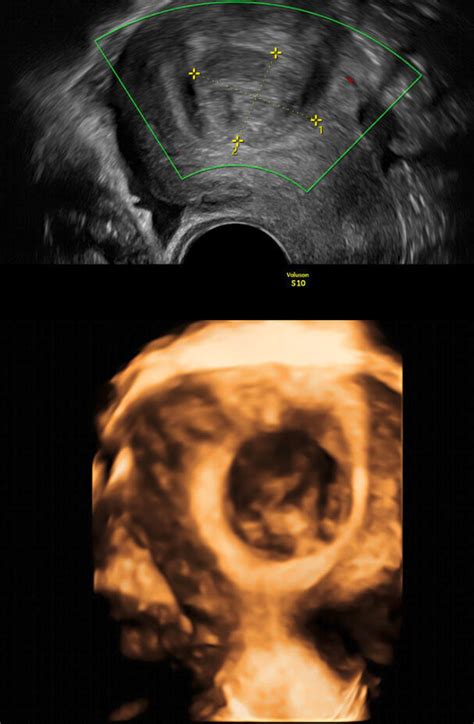

Für die Beurteilung der weiblichen Fruchtbarkeit ist es essenziell, die ovarielle Reserve zu kennen. Die Follikelzählung, die zu Beginn des Zyklus (zwischen dem 2. und 5. Tag) mittels Vaginalsonografie durchgeführt wird, liefert die genaueste Schätzung dieser Reserve. Die dabei beobachteten Follikel werden als Antralfollikel bezeichnet.

Die Anzahl der Antralfollikel gibt Aufschluss über die ovarielle Reserve:

- Angemessene oder normale ovarielle Reserve: 6 bis 10 Antralfollikel pro Eierstock.

- Niedrige ovarielle Reserve: Weniger als 6 Antralfollikel.

- Hohe ovarielle Reserve: Mehr als 12 Antralfollikel.

Im Rahmen eines natürlichen Zyklus wird aus den Antralfollikeln ein Follikel ausgewählt, der als dominanter Follikel bezeichnet wird. Dieser zeichnet sich durch seine Größe und sein schnelles Wachstum aus. Die anderen Follikel werden atretisch, das heißt, sie sterben ab und verschwinden.

Bevor die Ovulation stattfindet, erreicht der dominante Follikel typischerweise einen mittleren Durchmesser von 22 bis 24 mm (mit einer Bandbreite von 18 bis 36 mm).